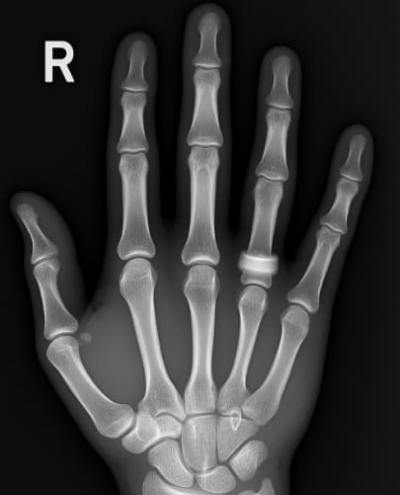

방아쇠 수지 증후군은 손가락을 굽힐 때 걸리는 듯한 느낌과 ‘딸깍’ 소리가 나는 대표적인 수부 질환입니다. 손가락을 반복적으로 사용하는 직업군이나 가사노동을 많이 하는 분들, 특히 40~60대 여성에게서 자주 발생하며, 증상을 방치할 경우 손가락이 굽은 상태나 편 상태로 고정되는 변형이 생길 수 있습니다. 오늘은 방아쇠 수지 증후군의 원인부터 주요 증상, 비수술적 방아쇠 수지 치료법과 수술적 치료법, 그리고 재발을 막기 위한 예방법까지 통합적으로 정리해 드리겠습니다.

방아쇠 수지 증후군은 손가락을 굽힐 때 힘줄이 통과하는 활차(pulley) 부위에서 염증이 발생해, 손가락이 펴지지 않거나 ‘딸깍’하며 갑자기 튕기는 증상을 말합니다. 주로 엄지, 중지, 약지에 잘 발생하며, 손가락의 건초염이 원인이 되는 경우가 많습니다.